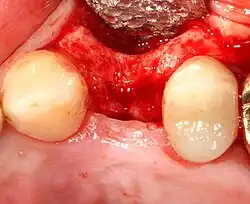

Most implant systems have five basic steps for placement of each implant:[28]: 214–221

- Soft tissue reflection: An incision is made over the crest of bone, splitting the thicker attached gingiva roughly in half so that the final implant will have a thick band of tissue around it. The edges of tissue, each referred to as a flap, are pushed back to expose the bone. Flapless surgery is an alternate technique, where a small punch of tissue (the diameter of the implant) is removed for implant placement rather than raising flaps.

- Drilling at high speed: After reflecting the soft tissue, and using a surgical guide or stent as necessary, pilot holes are placed with precision drills at highly regulated speed to prevent burning or pressure necrosis of the bone.

- Drilling at low speed: The pilot hole is expanded by using progressively wider drills (typically between three and seven successive drilling steps, depending on implant width and length). Care is taken not to damage the osteoblast or bone cells by overheating. A cooling saline or water spray keeps the temperature low.

- Placement of the implant: The implant screw is placed and can be self-tapping;[50]: 100–102 otherwise, the prepared site is tapped with an implant analog. It is then screwed into place with a torque controlled wrench[54] at a precise torque so as not to overload the surrounding bone (overloaded bone can die, a condition called osteonecrosis, which may lead to failure of the implant to fully integrate or bond with the jawbone).

- Tissue adaptation: The gingiva is adapted around the entire implant to provide a thick band of healthy tissue around the healing abutment. In contrast, an implant can be "buried", where the top of the implant is sealed with a cover screw and the tissue is closed to completely cover it. A second procedure would then be required to uncover the implant at a later date.